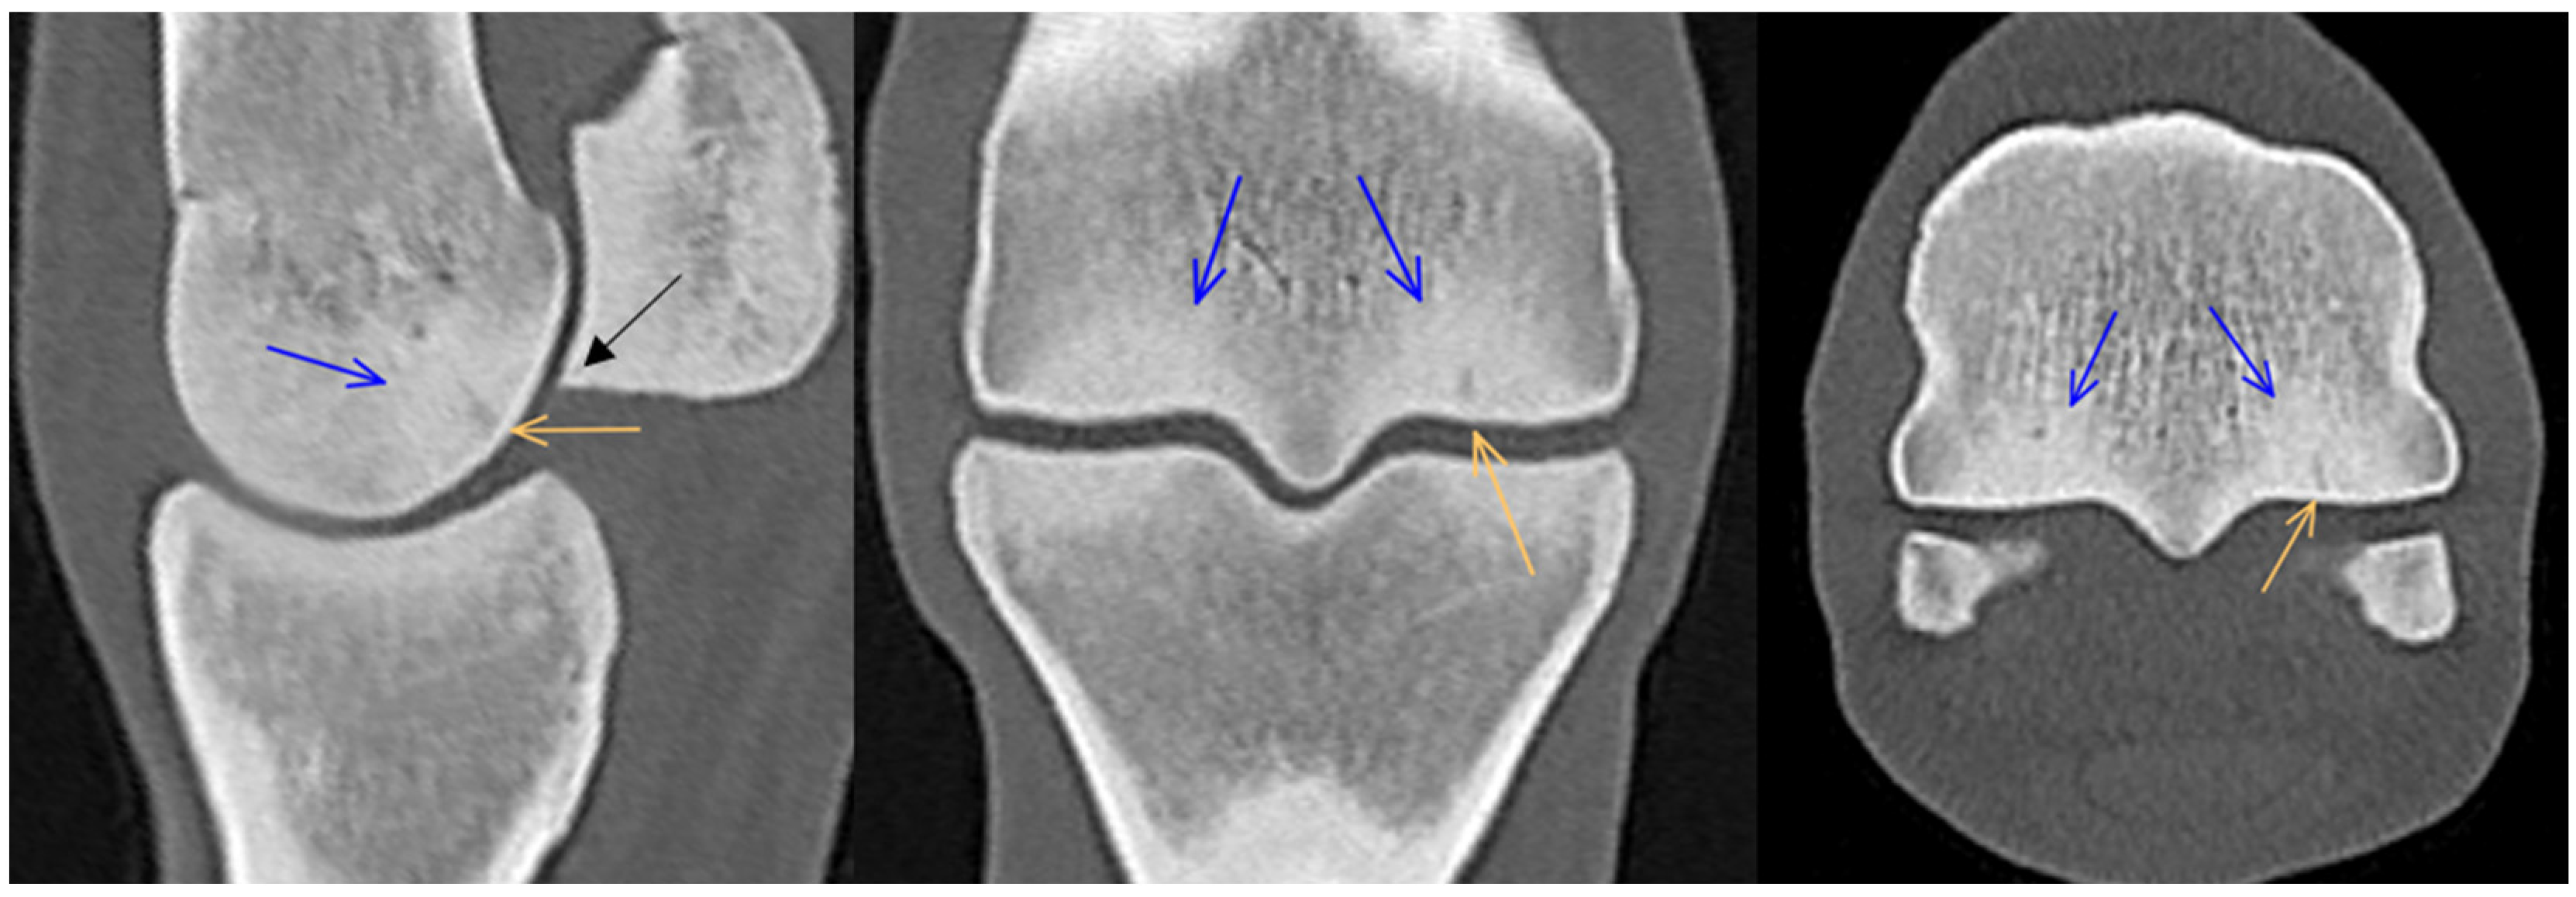

3.1. Third Metacarpal Bone

3.2. Proximal Phalanx

3.3. Proximal Sesamoid Bones